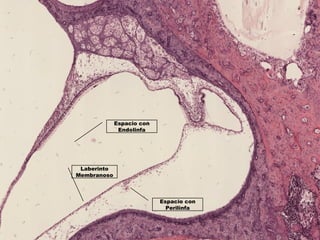

Espacio con

Perilinfa

Laberinto

Membranoso

Endolinfa